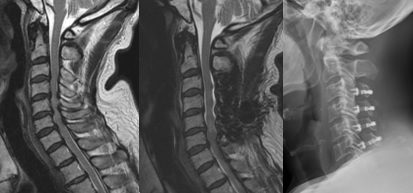

頚椎前方固定術/頚椎後方拡大術:頚椎椎間板ヘルニアや頚椎症性脊髄症に対して、神経の圧迫部位を除去や神経の通り道を広げ、インプラントや自分の骨を移植して固定することで、神経の除圧と症状の改善を目指します。